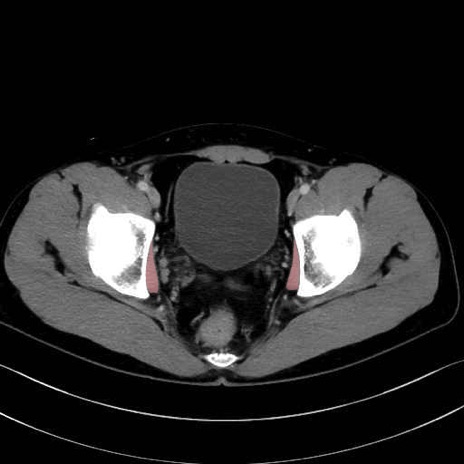

内閉鎖筋(obturator internus) のCT画像の解剖

内閉鎖筋 (Obturator internus)